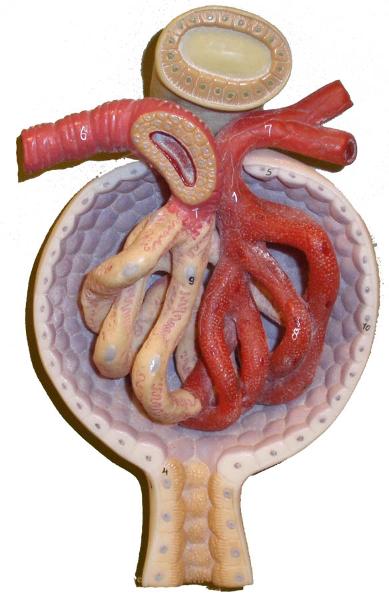

Afferent/efferent arteriole

Collecting duct

Descending/Ascending loop (of nephron)

Distal (convoluted) tubule

Glomerular capsule (=Bowman's capsule)

Glomerulus (=glomerular capillaries)

Juxtaglomerular apparatus

Nephron

Peritubular capillaries

Proximal (convoluted) tubule

Renal corpuscle